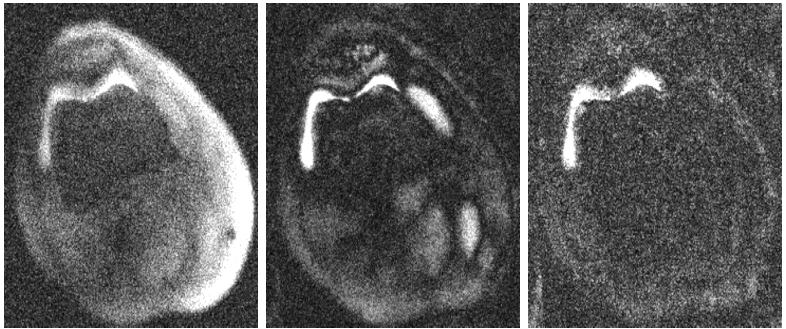

Fig. 2 shows the result of sampling from the prior distribution learned by the score model. As the sampling steps increase, the images converge to a sample from the prior. In Fig 3 we show the result of posterior sampling during the reconstruction iterations. The process begins with random noise and after the first step of posterior sampling, the images are similar to the adjoint of the under-sampled k-space data. The posterior sampling images are generated through annealed Langevin dynamics with the forward model and corresponding measurement gradient. Fig. 4 shows the result of posterior sampling compared to the T2Sh basis coefficient images on a scan from the test set. The reconstructed coefficient images are well in agreement with the ground truth coefficients. The low normalized root mean squared error (NRMSE) shows that posterior sampling through the score model is able to reconstruct basis coefficient images with good fidelity. Fig. 5 shows the virtual echo time images along the signal recovery curve after back-projecting with the basis. The plot shows the signal for two tissues (muscle and bone) where it can be observed that the curve from both the score model output and T2Sh output match closely.

Fig. 4 Reconstructed basis coefficient images compared to the ground-truth T2Sh reconstruction and the difference image which is shown with a 10X scale. The score model output images match the ground truth images within acceptable NRMSE error values.